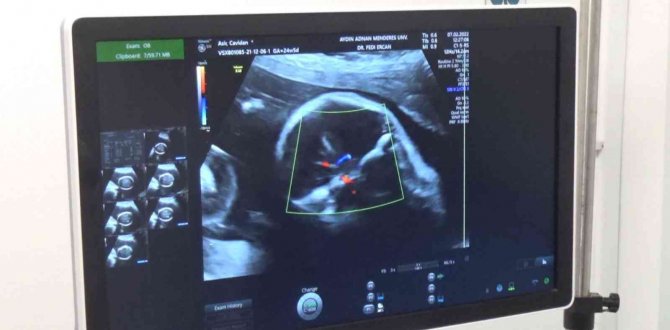

Aydın Adnan Menderes Üniversitesi (ADÜ) Araştırma ve Uygulama Hastanesi'nde bir ilk gerçekleştirildi. Tek yumurta ikizlerine hamile 40 yaşındaki Cavidan Aşır, gebelik kontrolleri sırasında beklemediği bir durum ile karşılaştı. İkizlere 6 aylık hamile Cavidan Aşır'ın bebeklerinden birinde ağır anomali tespit edildi. İkizler, Riskli Gebelik Takibi olarak bilinen Perinatoloji bölümü tarafından takibe alınırken, ailenin de kararı ile radyofrekans ablasyon işlemi uygulandı. Diğer bebeğin yaşam şansının artırılması ve sağlıklı bir şekilde dünyaya gelebilmesi amacıyla hasta olan ikizin 19 haftalıkken anne karnında kalbi durduruldu. Ülke genelinde sayılı merkezlerde gerçekleştirilen ve başarılı geçen operasyonun ardından anne karnındaki diğer bebeğin de gelişimi takip ediliyor.

İşlemin 19 haftalıkken uygulandığını annenin şuan 24 haftalık gebe olduğunu ve önemli bir takip süreci olduğunu ifade eden Kadın Hastalıkları ve Doğum Anabilim Dalı Perinatoloji Bilim Dalı Prof. Dr. Alper Tanrıverdi; "İkiz gebelikle alakalı bir sıkıntıdan dolayı müdahalede bulunuldu. Dr. Fedi Ercan öncesinde ameliyata yönelik gerekli hazırlıkları yaptı. Ameliyat yaklaşık 1 saat sürdü. Karın cildinden bir iğne ile radyofrekans dediğimiz bir sistemle hastaya müdahalede bulunuldu. Ameliyat başarılı sonuçlandı diye düşünüyoruz ama tabi daha hastanın takibi devam edilecek" dedi.

Kontrolleri sırasında ikizlerden birinde ağır anomali olduğunu tespit ettiklerini ifade eden Kadın Hastalıkları ve Doğum Anabilim Dalı Perinatoloji Bilim Dalı Dr. Öğr. Üyesi Fedi Ercan ise "Perinatoloji, ülkemizde daha yeni tanınmaya başlayan bir branş. Türkiye'de çok sınırlı bir merkezde yapılıyor. Perinatoloji açısından ülkemiz için yabancı değil bu işlemler ama yaygın değil. Üniversitemizde de hocamızla beraber ilk kez yaptığımız bir işlem. Cavidan Hanım çok uyumlu bir hastaydı bizim için. Yaşı 40, ilk gebelik ve çocuklardan birinde özellikle beyinciği de içine alan çok ağır bir anomalisi vardı ve gerçekten kendisi bize, biz de kendisine güvendik. Sonuçta bu işlemi yaptık. Bebeklerden birisinin yaşamına son verdik çünkü ağır bir anomalisi vardı. Burada diğer sağlıklı görünen çocuğun yaşam şansını artırmak ve gebelikte erken doğumu da önlemek adına maalesef ağır engelli ve beyin anomalisi olan çocuğumuzun yaşamını sonlandırmak için bir seçenekti bu yaptığımız işlem. Radyofrekans ablasyon işlemi. Engelli çocuğun kalbi durdurularak bu sayede çok ağır maluliyet oluşturacak engelli çocuğun ikiz eşinin sağlıklı bir şekilde dünyaya gelmesi sağlandı. Zamanında bir doğum için öteki çocuğa şans tanımış olduk. Zamanında doğumu için de önemliydi tek kese ikizi ve tabiki takip etmemiz gereken de bir süreç var. Sağlıksız olarak dünyaya gelecek ağır engelli çocukta hayatı boyunca çocuklukta maluliyet oluşturacak bir durum olacaktı. Biz bunun önüne geçmiş olduk. Perinatoloji zaten bunun için var, riskli gebelik ve artık Türkiye'de dört bir yanda Perinatoloji uzmanları var. Bu işlemler özellikli işlemler ve uzmanları tarafından yapılıyor. Umarım hem anne hem bebek, doğum sürecine kadar sıkıntısız bir süreç geçirir" dedi.